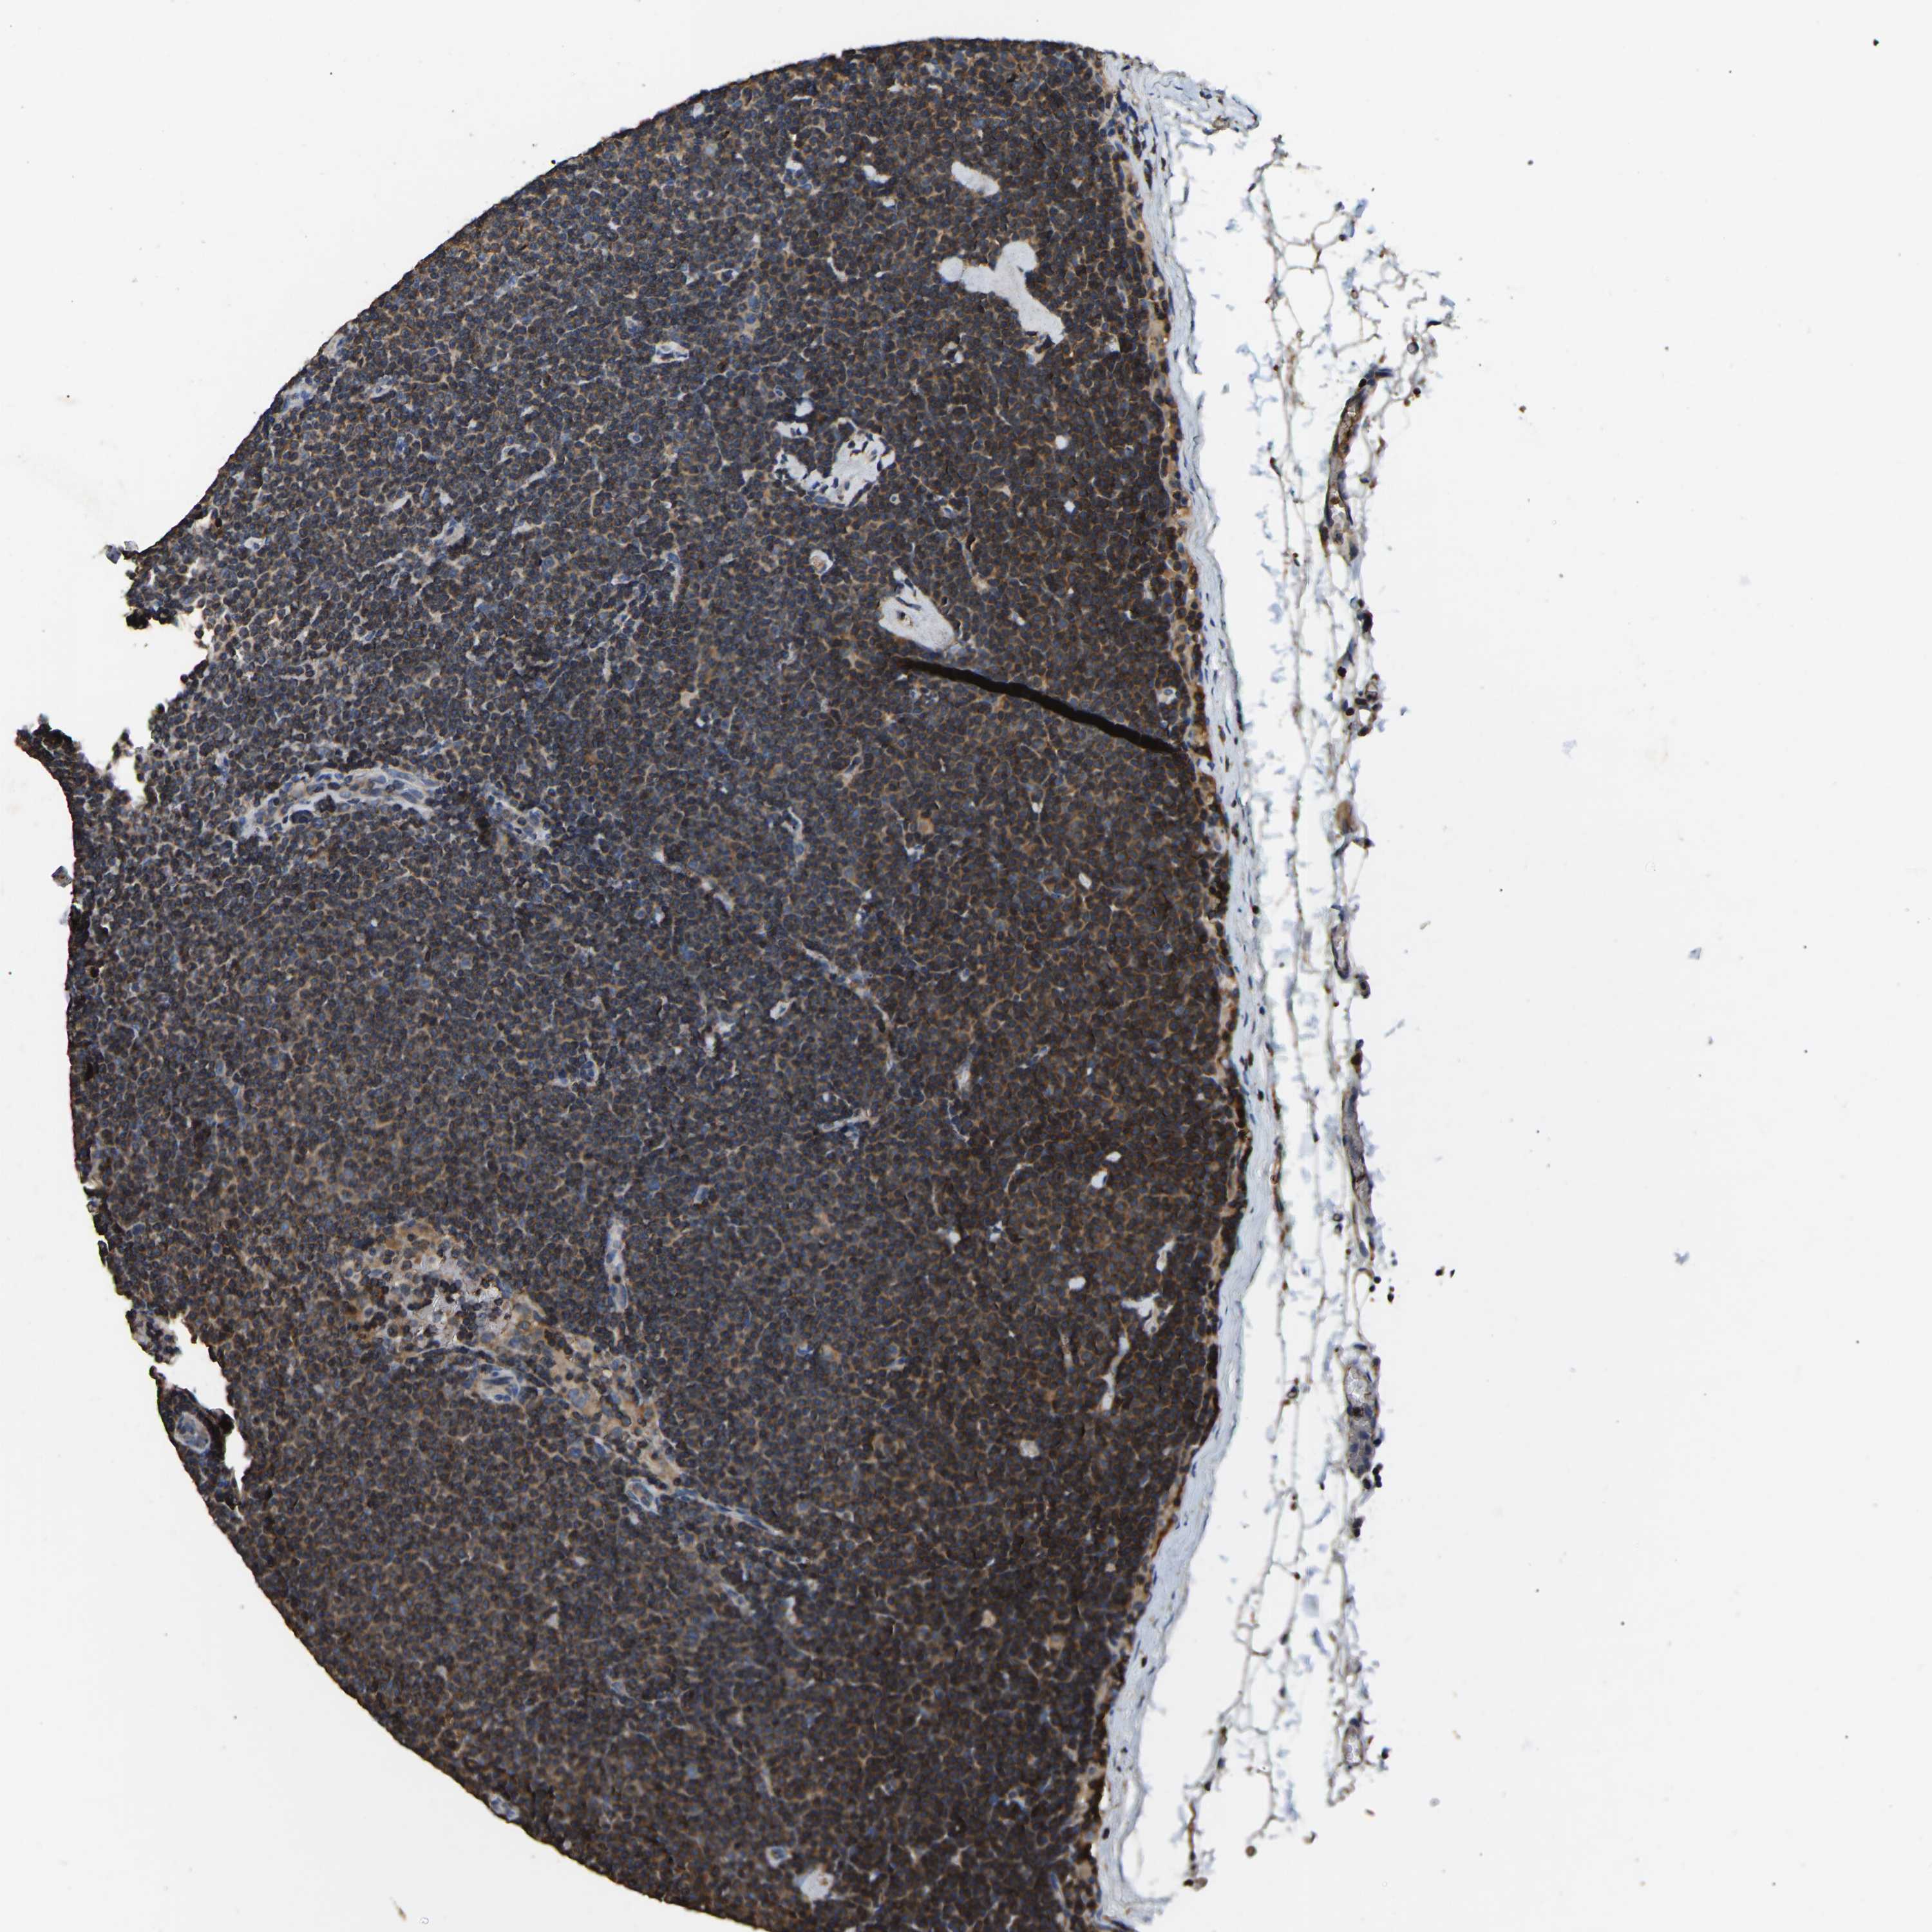

CANCER LYMPHOMA Show tissue menu

LYMPHOMA - Protein expressioni

A mouse-over function shows sample information and annotation data. Click on an image to view it in a full screen mode. Samples can be filtered based on level of antibody staining by selecting one or several of the following categories: high, medium, low and not detected. The assay and annotation is described here.

Each image is clickable and will lead to virtual microscopy that enables deeper exploration of all samples and also displays staining intensity scores, fraction scores and subcellular localization as well as patient and tissue information for each sample.

Antibody HPA018110

Antibody HPA018125

Hodgkin's disease, NOS

Malignant lymphoma, non-Hodgkin's type, High grade

Malignant lymphoma, non-Hodgkin's type, Low grade